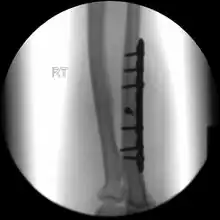

Undisplaced isolated ulna fracture

If the fracture is not significantly displaced, is stable, and is not associated with another fracture, it may be treated with a cast for around five to six weeks.[3] This includes fractures that are less than 50% displaced and less than 10 degrees angulated.[6]

During the recovery period healing can be followed up with x-rays.[3] Heavy lifting should be avoided.[3] After the cast has been removed exercises are encouraged and full strength is regained over time.[3] Treatment may may also be with splinting and early movement.[2]

When there is a displaced fracture or when the radioulnar joints are involved an operation is often performed, using either flexible rods or screws and plates in order to reduce the fracture and immobilise the bone.[3]